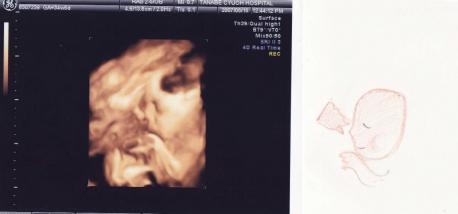

日時:2007年8月18日

場所:ママのおなかの中 (34週間と5日)

大きさ:BPD(頭の直径):8.59cm

FTA(腹部の断面積):69.75cm2

FL(大腿部の長さ)6.06cm

EFW(推定体重):2286g

後期の写真の中で一番きれいかも。

こんな写真で「かわいい♪」と思えるのよねん。